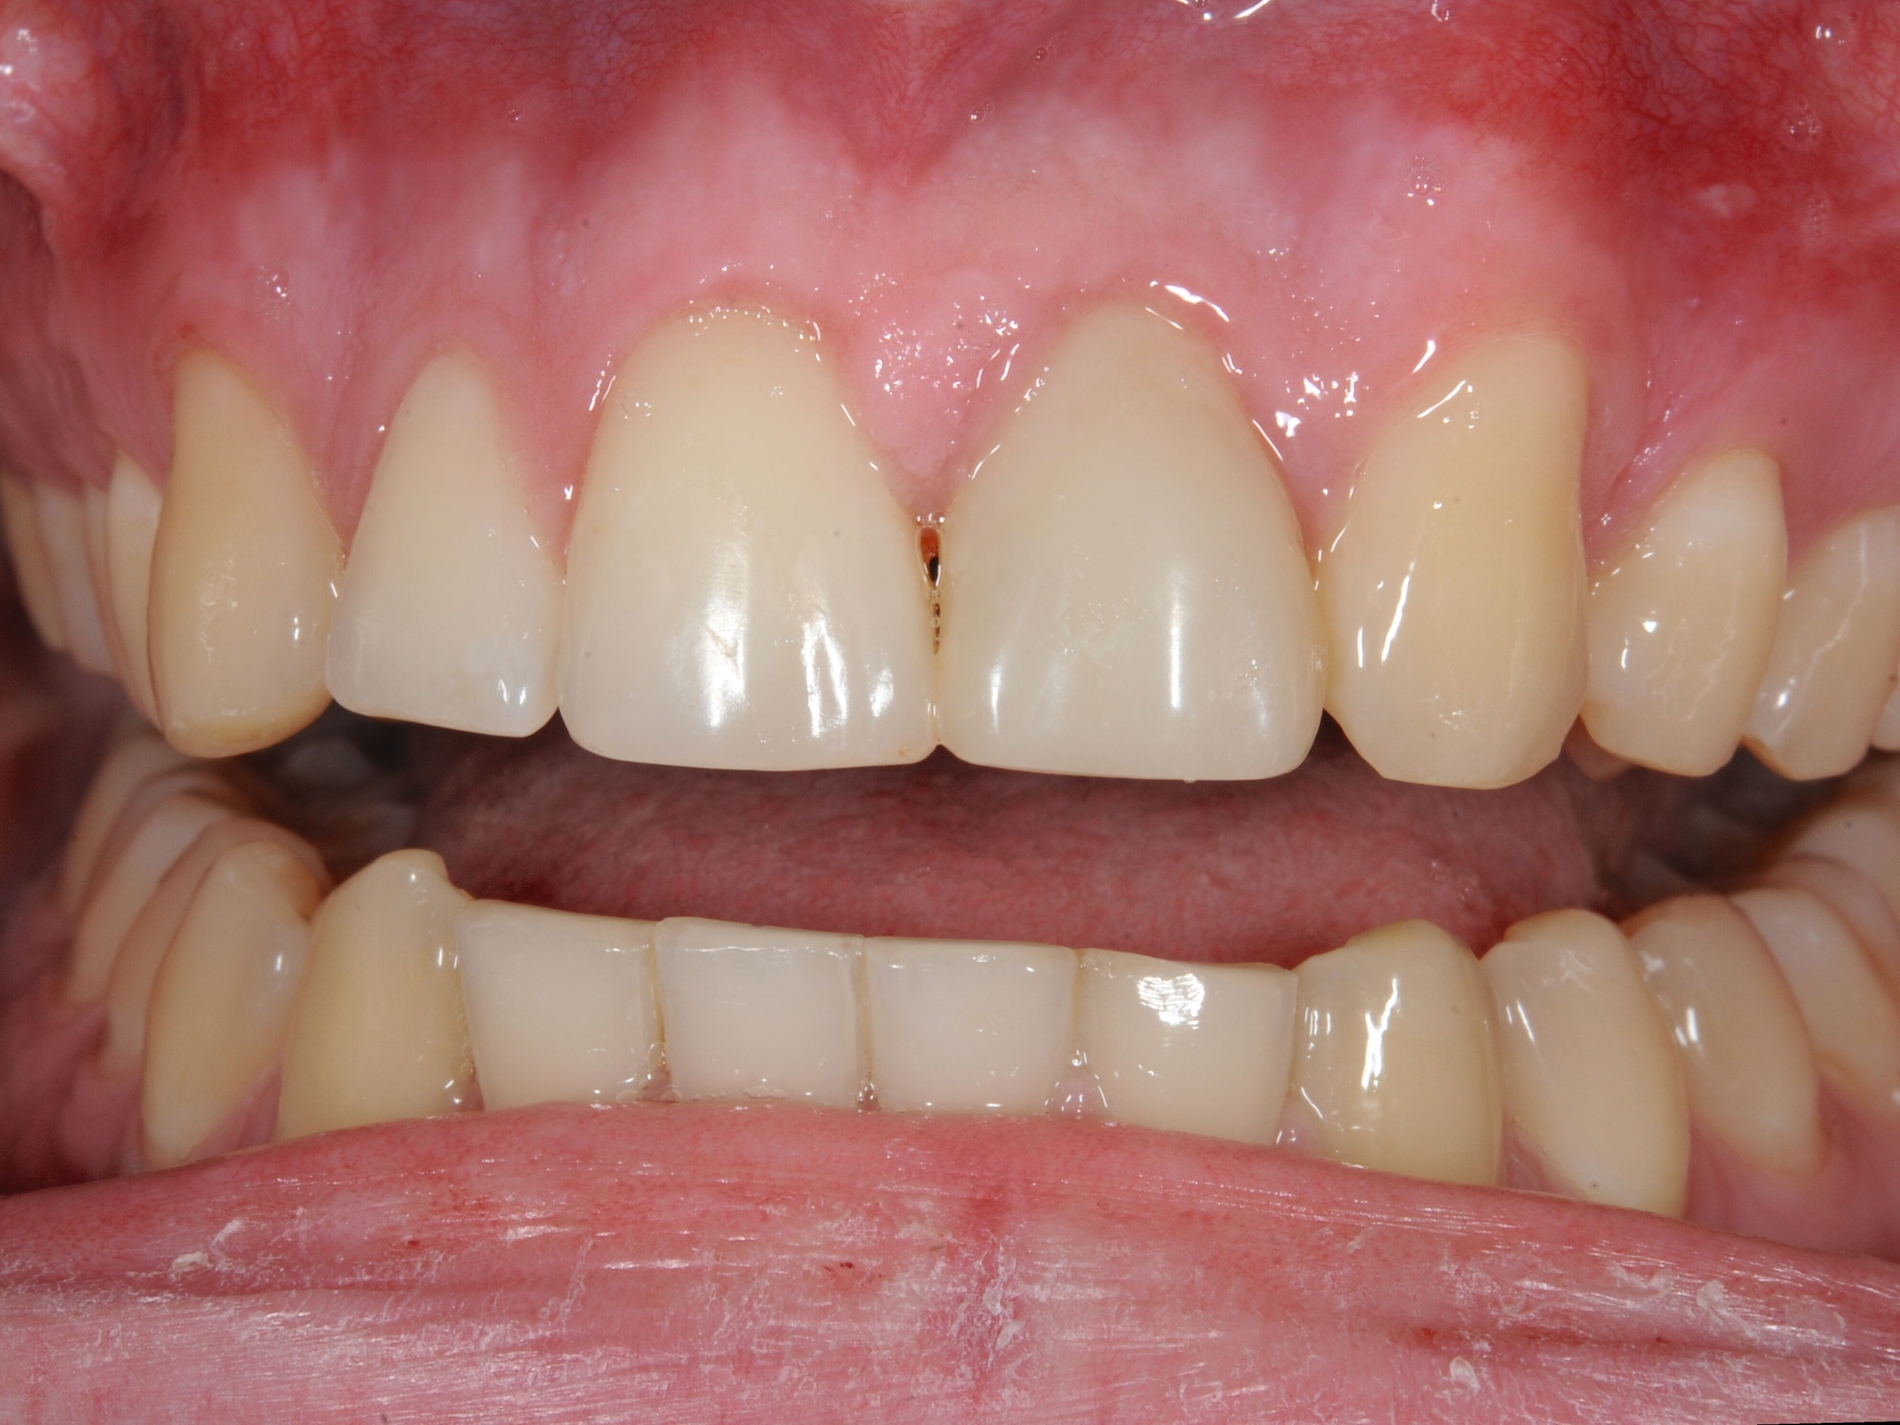

Scheint nach Kronen-Wurzel-Frakturen der Zahnerhalt grundsätzlich möglich, stehen verschiedene Behandlungsalternativen zur Verfügung, die maßgeblich davon abhängen, ob die Defektlokalisation eine suffiziente restaurative Versorgung zulässt beziehungsweise mit welchen Mitteln diese erreicht werden kann [Krastl et al., 2011]. Neben der adhäsiven Fragmentbefestigung, der restaurativen Versorgung der zugänglichen supragingivalen Bereiche, der restaurativen Versorgung nach chirurgischer Kronenverlängerung oder chirurgischer Extrusion kann auch eine restaurative Versorgung durch eine vorherige kieferorthopädische Extrusion ermöglicht werden.

Im Hinblick auf Kronen-Wurzel-Frakturen beziehungsweise zervikale Wurzelfrakturen stellt die kieferorthopädische Extrusion eine schonende Behandlung von Vorteil dar, da bei schneller Extrusion die Gingivahöhe erhalten bleibt. Prapas et al. unterscheiden hierbei die klassische langsame kieferorthopädische Extrusion (maximal 1-2 mm pro Monat) durch leichte Kräfte und die schnelle Extrusion, bei der der Zahn mit starken Kräften aus der Alveole bewegt wird (3-4 mm pro Monat) [Prapas et al., 2008]. Während bei der langsamen Extrusion Alveolarknochen und Weichgewebe dem Zahn in gleichem Ausmaß zu folgen scheinen, bleiben bei der schnellen Extrusion die umgebenden Gewebe weitgehend zurück [Prapas et al., 2008].

Um bei einer schnellen kieferorthopädischen Extrusion sicherzustellen, dass keine limbale Knochenapposition durch eine Mitwanderung der Gingiva erfolgt, sollte dabei in regelmäßigen Abständen eine suprakrestale Fibrotomie durchgeführt werden [Carvalho et al., 2006]. Wird bei der kieferorthopädischen Extrusion keine regelmäßige suprakrestale Fibrotomie durchgeführt, kommt es auch zu einer Koronalverlagerung von Gingiva und Knochen. Dies ist bei einer nachfolgend angestrebten restaurativen Versorgung, die die Frakturränder in der Restauration fassen soll, in der Regel nicht erwünscht [Carvalho et al., 2006].

Langsame kieferorthopädische Extrusionen mit moderaten kieferorthopädischen Kräften ohne suprakrestale Fibrotomien hingegen können indiziert sein, wenn Gewebe aufgebaut werden soll oder Gingivaverläufe kieferorthopädisch korrigiert werden sollen [Prapas et al., 2008; Bauer et al., 2022].